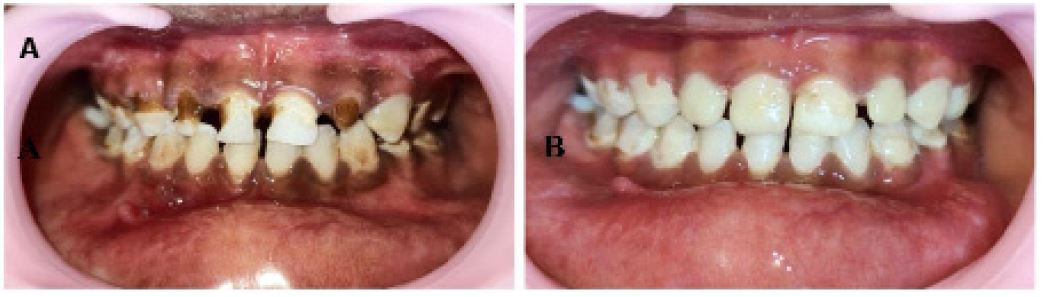

A young girl reported to the Department of Pediatric and Preventive Dentistry with the chief complaint of pain and swelling in the lower jaw. The patient had a history of falling from height while playing 10 days ago. The history of unconsciousness, vomiting, ENT bleeds, and convulsions after the fall was negative. The patient went to a local hospital, but no intervention was done. The extra-oral examination revealed a diffuse swelling over the bilateral lower one-third of the face, which was tender on palpation. Lacerations were present over the chin region on palpation, associated with deranged occlusion leading to the appearance of an open mouth (Figure 1A). On palpation, step deformity and tenderness were noted over the left parasymphysis region and the lower border of the jaw. An intraoral examination indicated a gap in the tooth left mandibular canine and primary first molar regions. Teeth were not in proper occlusion and slight midline deviation was seen. Multiple carious teeth were present (Figure 1B).

Figure 1: (A) Profile photograph showing lacerations over chin and open bite appearance. (B) Intraoral photograph showing deranged occlusion and gap between left mandibular primary canine and first molar region.

In the second post-operative week, IMF was removed, no mobility was present at the fracture site, and occlusion was satisfactory. At one month follow-up, clinical examination revealed satisfactory occlusion (Figure 5A). The carious teeth were restored with restorative glass ionomer cement (GC Fuji II) and light cure composite (3MTM FiltekTM Universal restorative) (Figure 5B). Radiographic presentation on one-month follow-up revealed complete healing of the fracture site (Figure 6). Postoperative recovery was uneventful, and the patient was reviewed monthly for 6 months (Figures 7,8).

Figure 5: (A) Intraoral photograph showing satisfactory occlusion at 1-month follow-up.

(B) Post-operative intraoral photograph after restorations.